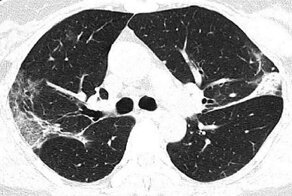

Галина Красноперова пять лет приносит домой не конфеты и цветы - родственники пациентов реанимации редко их приносят - не до того, - а записки пациентов, с помощью которых они общаются с врачами. Лежачие больные могут неделями и месяцами находиться на искусственной вентиляции легких, и если пребывают в сознании, то говорить не могут, а писать пытаются.

Иногда эти записки оказываются последним делом пациента, если он умирает. А те, кто выздоравливают, по счастью и не вспоминают о том, как на клочке бумаги просили медсестру об одеяле или спрашивали, какое сегодня число и месяц.

Читать эти строчки страшно. Но именно они лучше картинок объясняют, что чувствует человек, находящийся на ИВЛ. Врач объясняет, что приносила эти записки домой, потому что не смогла их выбросить. Она знала, как тяжело давалось пациентам каждое усилие.